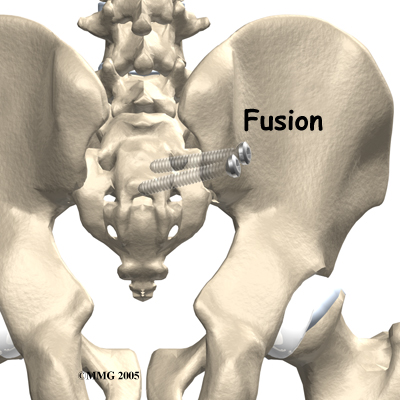

Surgery

Surgery may be considered if other treatments don't work. Surgery consists of fusing the painful SI joint. A fusion is an operation where the articular cartilage is removed from both ends of the bones forming the joint. The two bones are held together with plates and screws until the two bones grow together, or fuse, into one bone. This stops the motion between the two bones and theoretically eliminates the pain from the joint.

This is a big operation and is not always successful at relieving the pain. The operation is not commonly performed unless the pain is debilitating. SI joint pain is seldom this severe.